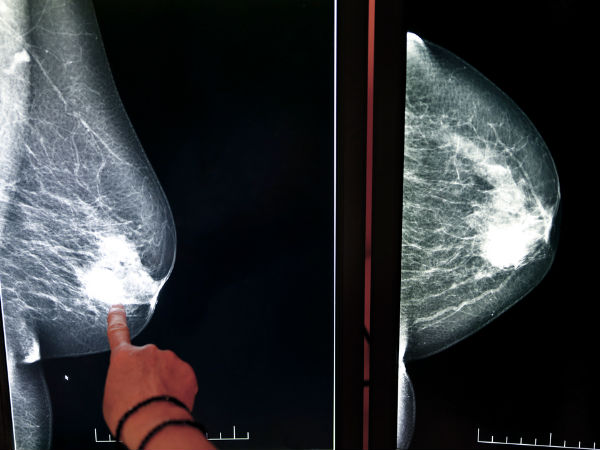

ഇതെക്കുറിച്ചു കൂടുതല് പഠനം നടത്തിയ ഡോക്ടര് റോബെര്ട്ട് ജോണ്സണ് റൂട്ട് കനാലും ബ്രെസറ്റ് ക്യാന്സറും തമ്മിലുള്ള ബന്ധത്തെക്കുറിച്ചു വിശദീകരിയ്ക്കുന്നു. ബ്രെസ്റ്റ് ക്യാന്സര് ബാധിച്ച 93 ശതമാനം സ്ത്രീകളിലും റൂട്ട് കനാല് നടത്തിയതായാണ് അദ്ദേഹത്തിന്റെ ഗവേഷണഫലം. അശ്ലീലചിത്രം കാണുന്നവനെ കെട്ടിയാല് പെട്ടു.....

ട്യൂമറിനെ തടയാന് സഹായകമായ പ്രോട്ടീന് ഉല്പാദനം തടയാന് ഇത്തരം ബാക്ടീരിയകള്ക്കു കഴിയും. ഇതാണ് ക്യാന്സര് കാരണം.